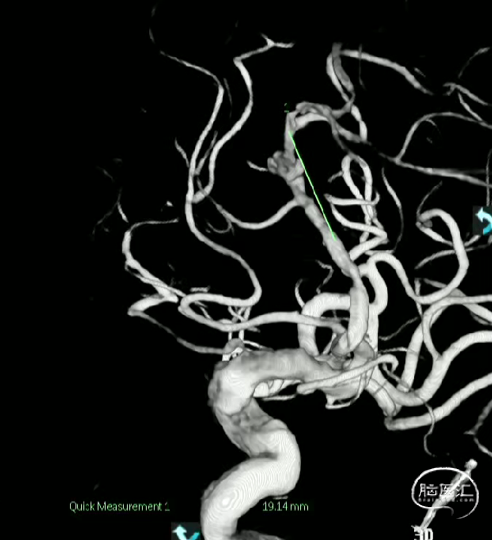

术前测量

远端锚定点:1.5mm

瘤颈远端:1.53mm

瘤颈近段:2.4mm

动脉瘤瘤体直径:4.40mm